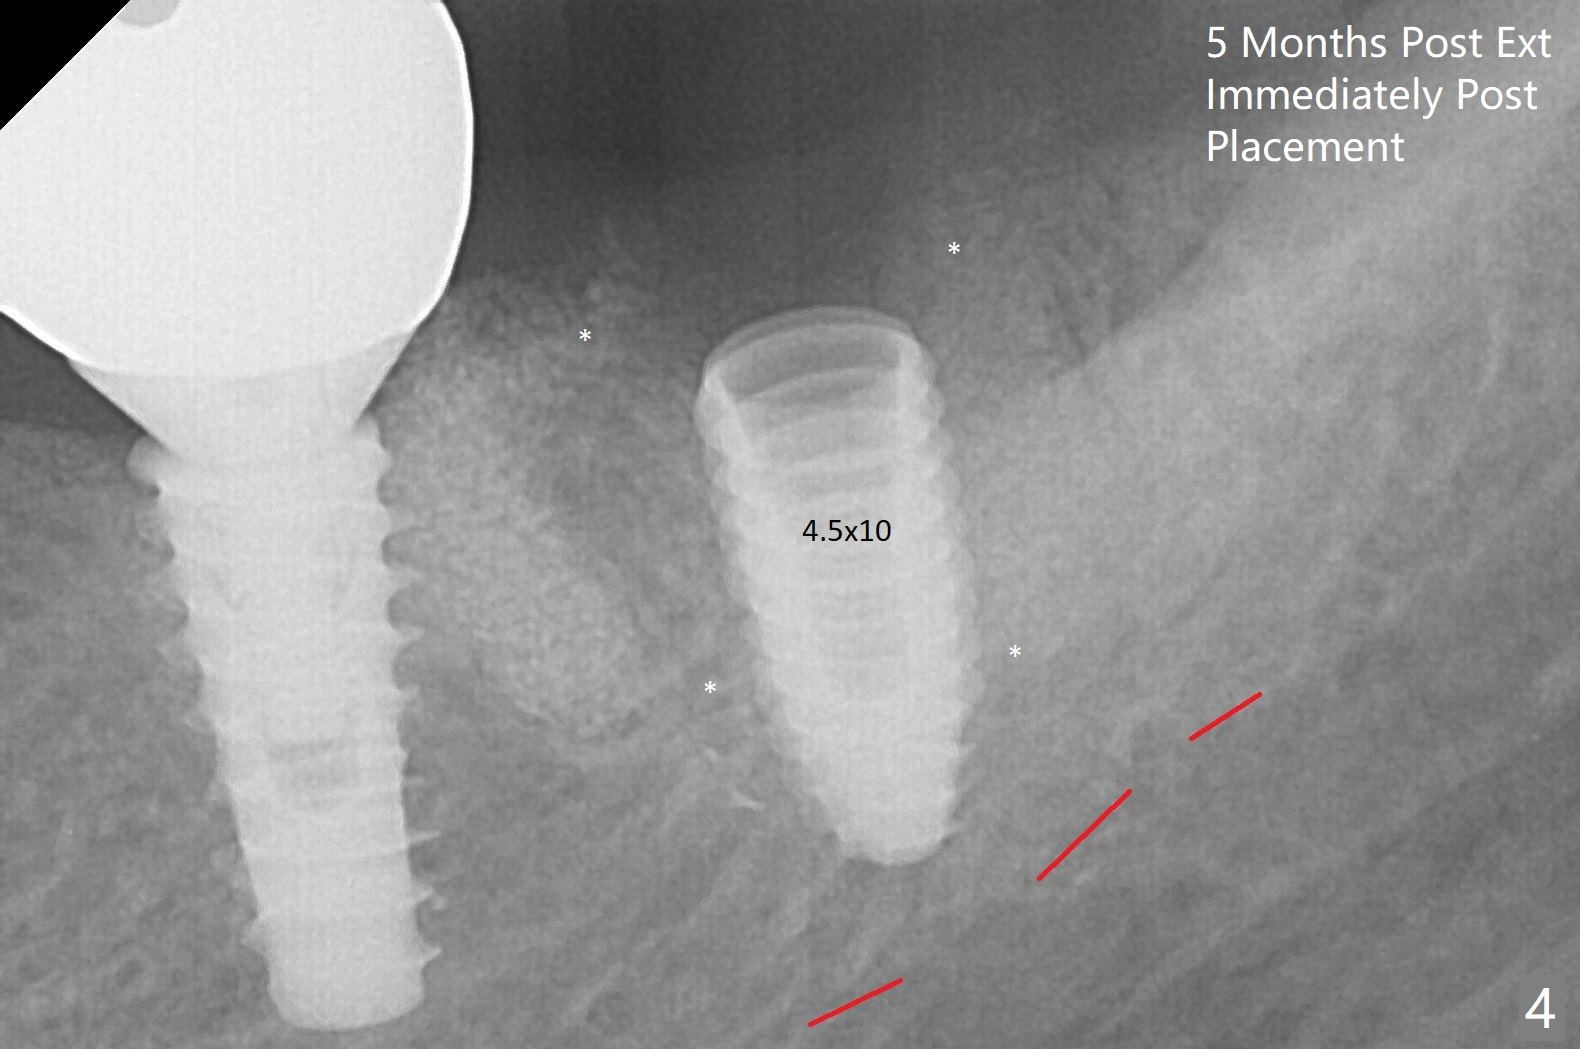

A 55-year-old woman is going to have implant placement at #18 using surgical guide 5 months post socket preservation (Fig.1). The bone density of initial osteotomy until 3.5x7.3 mm drill seems to be soft (Fig.1,2). Underprep is decided for the remaining osteotomy (Fig.3). The last drill is 3.5x10 for 4.5x10 mm implant (Fig.4). In fact initial insertion torque is >55 Ncm. The implant has to be backed up several times to get final torque ~ 35 Ncm. Retrospectively the bone density of the lower portion of the osteotomy is higher than that of the upper one (compare Fig.2,3). There is crestal bone (grafted one *) resorption 4 months postop (Fig.5).